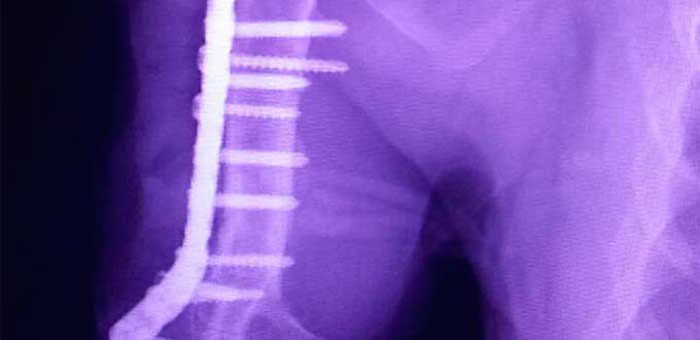

Ciudad de México, 27 de marzo (SinEmbargo/Pulso).- Aproximadamente a las 4:30 de la tarde de este domingo, Nala, la puma a la que gracias a diversas donaciones, le colocaron una placa de titanio para corregir una fractura de húmero, fue operada con éxito en una clínica privada del poniente de la ciudad de San Luis Potosí.

La placa era indispensable para evitar que la lesión se continuara deteriorando por la acción de los huesos desprendidos.